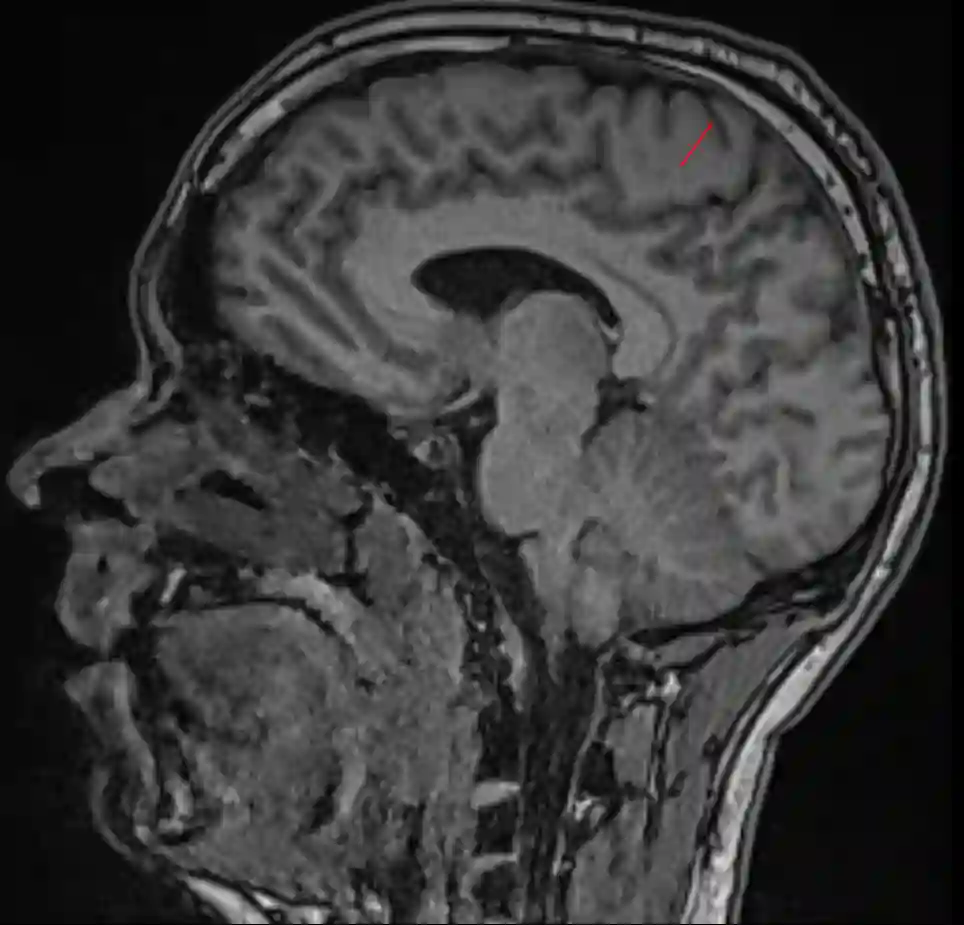

Sulcus centralis sagittal MRI

Sagittales MRI des Schädels mit Markierung des Sulcus centralis (roter Pfeil).

Sagittales MRT

Im sagittalen MRT Bild befindet sich der Sulcus centralis direkt anterior des Sulcus cinguli.

Sulcus cinguli und Sulcus centralis im MRT

Darstellung des Sulcus cinguli (blau) und des Sulcus centralis (rot) im sagittalen MRT Bild.